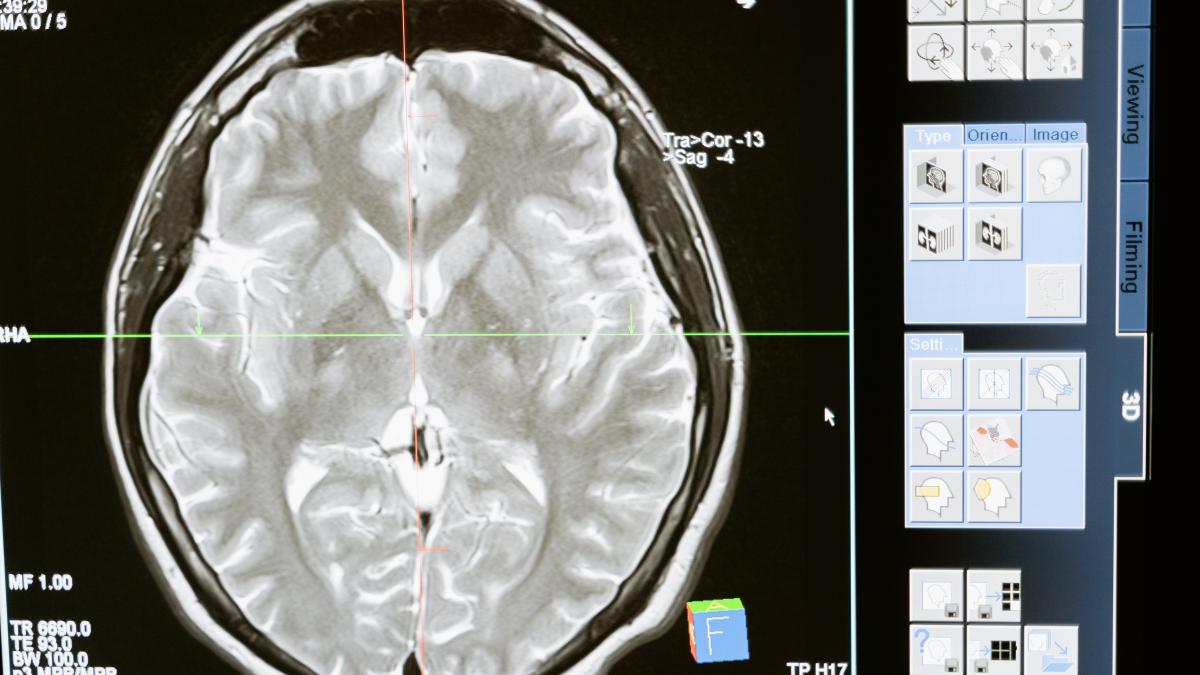

Pe când, uneori, AVC-ul ischemic se instalează insidios, încetişor, cu simptome prevestitoare, dar care nu sunt atât de intense. O durere de cap uşoară, ameţeli, poate mici tulburări de vedere, astea pot intra în cortegiul de simptome nu atât de spectaculoase. Diferenţierea e dificilă în primă instanţă, iar certitudinea o primim prin investigaţii imagistice într-o unitate de primiri urgenţe", a mai declarat dr. Pandrea.